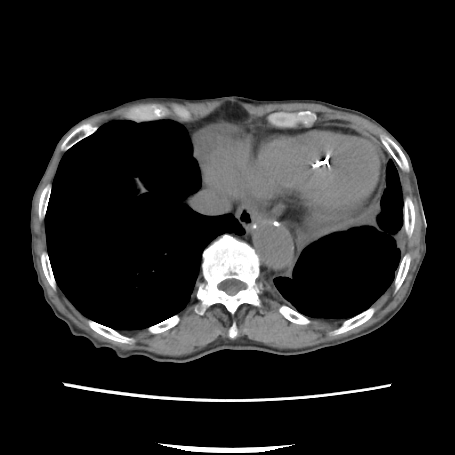

80歳代男性.左鼠径部に違和感と疼痛あり.疼痛が徐々に増強し,下腹部に広がったため当院に救急搬送された.

下腹部に自発痛・圧痛あり.反跳痛なし.左鼠径部に3 cm程の隆起あり.

Q1:単純CT(図1,2)の異常所見は?

図1 腹部単純CT(横断像)

誌面掲載画像は赤枠で示す